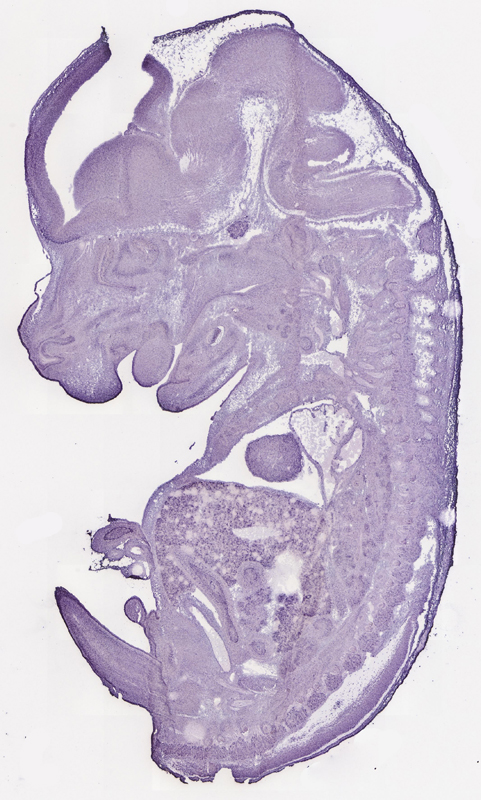

Specimen

euxassay_003443_18:

embryonic day 14.5

euxassay_003443_19: